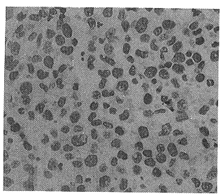

2.2 Lewis肺癌细胞形态测量和DNA含量测定 经Feulgen染色的组织切片,核呈深红色,胞浆不着色。Ⅰ组核大,多呈空泡状,染色质聚集成块,核分布紧密,核浆比例大(图1)。用药组核缩小,染色质均匀分布,核间隙增宽,核浆比例缩小(图2)。从Ⅰ组至Ⅳ组,核面积、周长、平均直径、积分光密度均依次减小,而形状因子均依次增大(表1)。上述参数各用药组与对照组比较:Ⅱ与Ⅰ比,差异有显著性(P<0.05);Ⅲ、Ⅳ与Ⅰ比,差异有显著性(P<0.01)。各用药组之间比较:Ⅲ、Ⅳ与Ⅱ比,差异有高度显著性(P<0.01);Ⅳ与Ⅲ比,差异有显著性(P<0.05)。这说明,用药后肿瘤细胞体积缩小,生长受抑制,核DNA含量(积分光密度值)降低,肿瘤细胞核增殖能力减弱。其中联合用药效果最好,其次为单用紫杉醇组。

图1. 组Ⅰ肿瘤结节组织切片,核大,分布紧密,多呈空泡状,异型性大 Feulgen染色 ×466

Fig 1 Histological section of tumor for group Ⅰ (The nucleus became big and dense in distribution, most cases with vaculization and obvious atypia. Feulgen staining ×466)